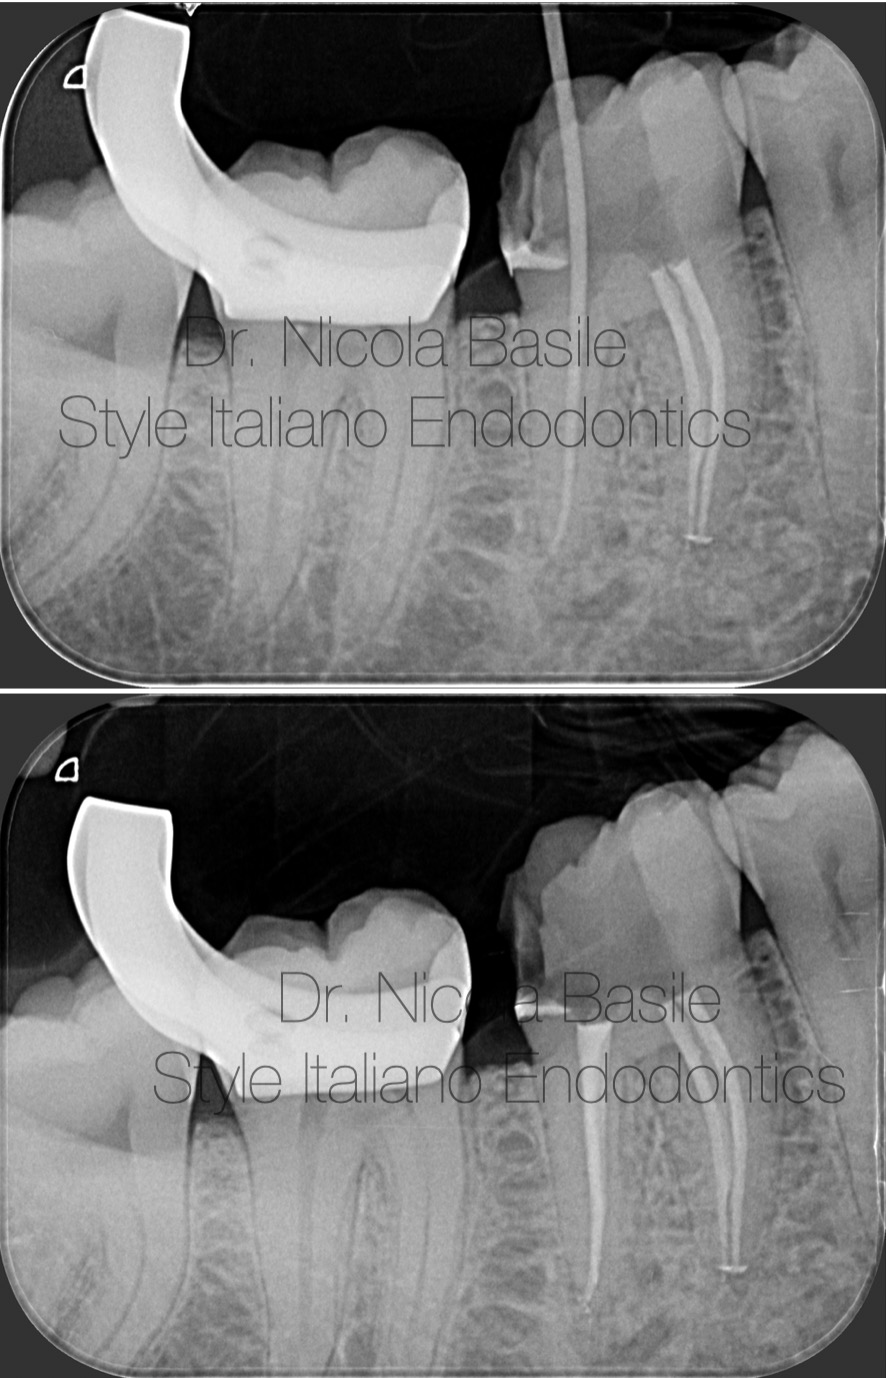

Control Xray

Fig. 14

Follow up 3 years

Fig. 16